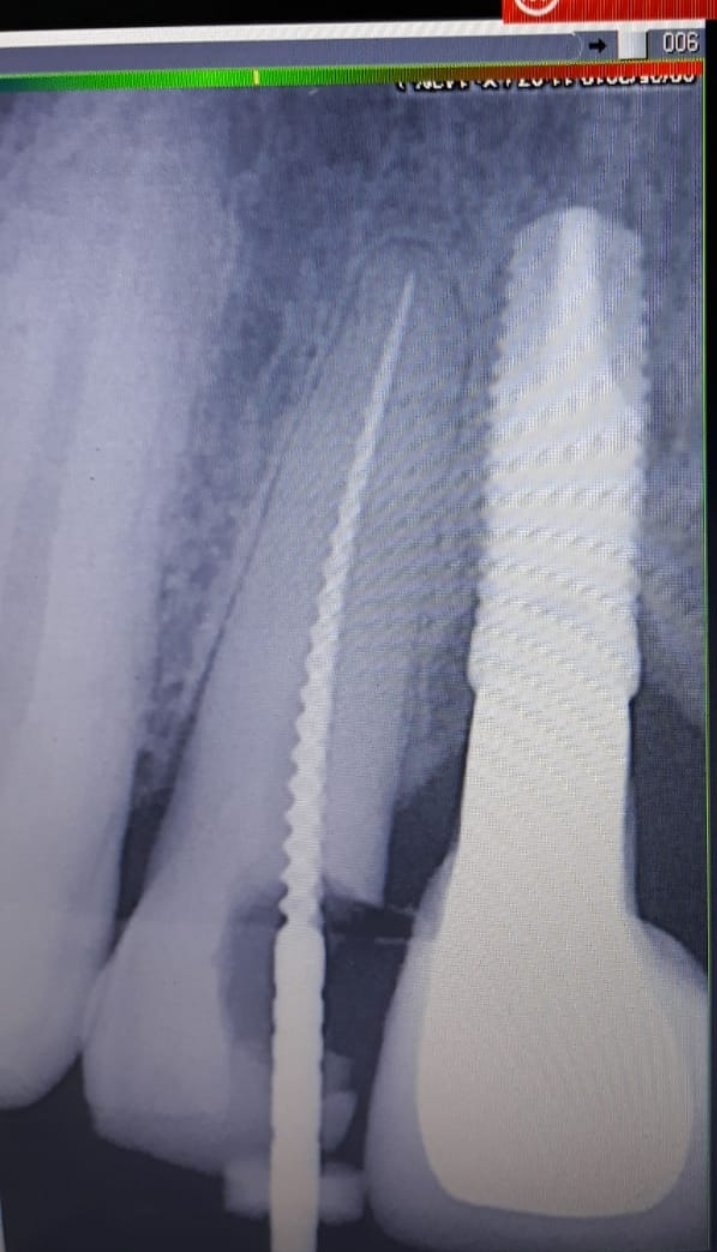

Hola, tengo dudas, creo que es bti conexión interna pero parece que lleva conectado un pilar... La corona por dentro tiene uan retención en forma de "estrella" parecid a synocta. [...]